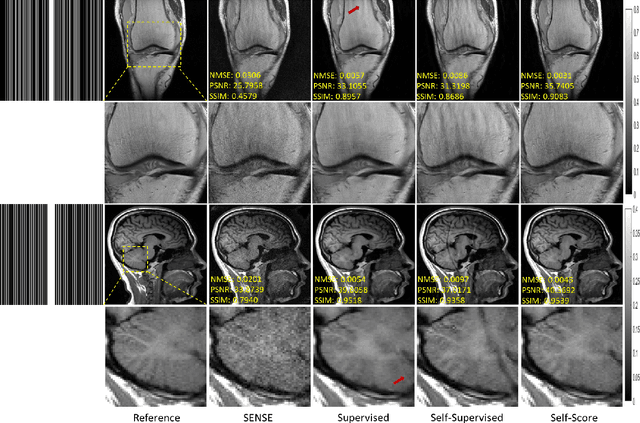

Abstract:Diffusion model has been successfully applied to MRI reconstruction, including single and multi-coil acquisition of MRI data. Simultaneous multi-slice imaging (SMS), as a method for accelerating MR acquisition, can significantly reduce scanning time, but further optimization of reconstruction results is still possible. In order to optimize the reconstruction of SMS, we proposed a method to use diffusion model based on slice-GRAPPA and SPIRiT method. approach: Specifically, our method characterizes the prior distribution of SMS data by score matching and characterizes the k-space redundant prior between coils and slices based on self-consistency. With the utilization of diffusion model, we achieved better reconstruction results.The application of diffusion model can further reduce the scanning time of MRI without compromising image quality, making it more advantageous for clinical application